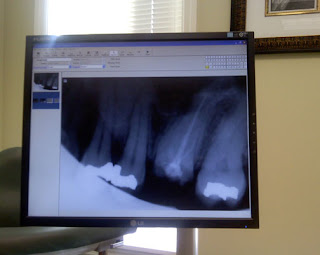

Anyway, my nubbins of a tooth looked zombie-ish to me. I even thought I could hear it’s little voice yelling, “brrrraaaaaaaaiiiiiinnnnns,” but I wasn’t certain about that. I won’t scare you with an actual photo (pretty gross in there), but I will show you the x-ray. I think you can figure out which one’s the zombie.